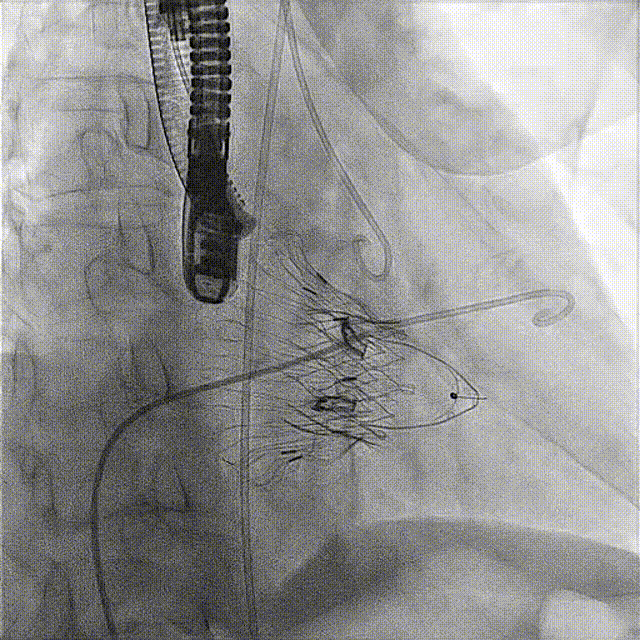

術(shù)前DSA

術(shù)前經(jīng)過全面系統(tǒng)的評估后,考慮患者存在高齡、心功能減低、三尖瓣瓣環(huán)重度擴張(三尖瓣極重度反流)等高危因素,因此廈心結(jié)構(gòu)心團隊聯(lián)合超聲心動、麻醉及護理團隊,制定了詳盡的圍術(shù)期治療方案及術(shù)中治療難點預(yù)案。術(shù)中,由王焱院長主刀,在蘇茂龍主任超聲心動團隊的輔助,上海市第一人民醫(yī)院陸方林主任的協(xié)助下,僅用時30分鐘,即順利完成了三尖瓣原位置換的手術(shù)。術(shù)中患者血流動力學(xué)穩(wěn)定,術(shù)后即刻顯示LuX-Valve Plus瓣膜位置良好,固定穩(wěn)定,瓣膜功能正常,無瓣周漏。